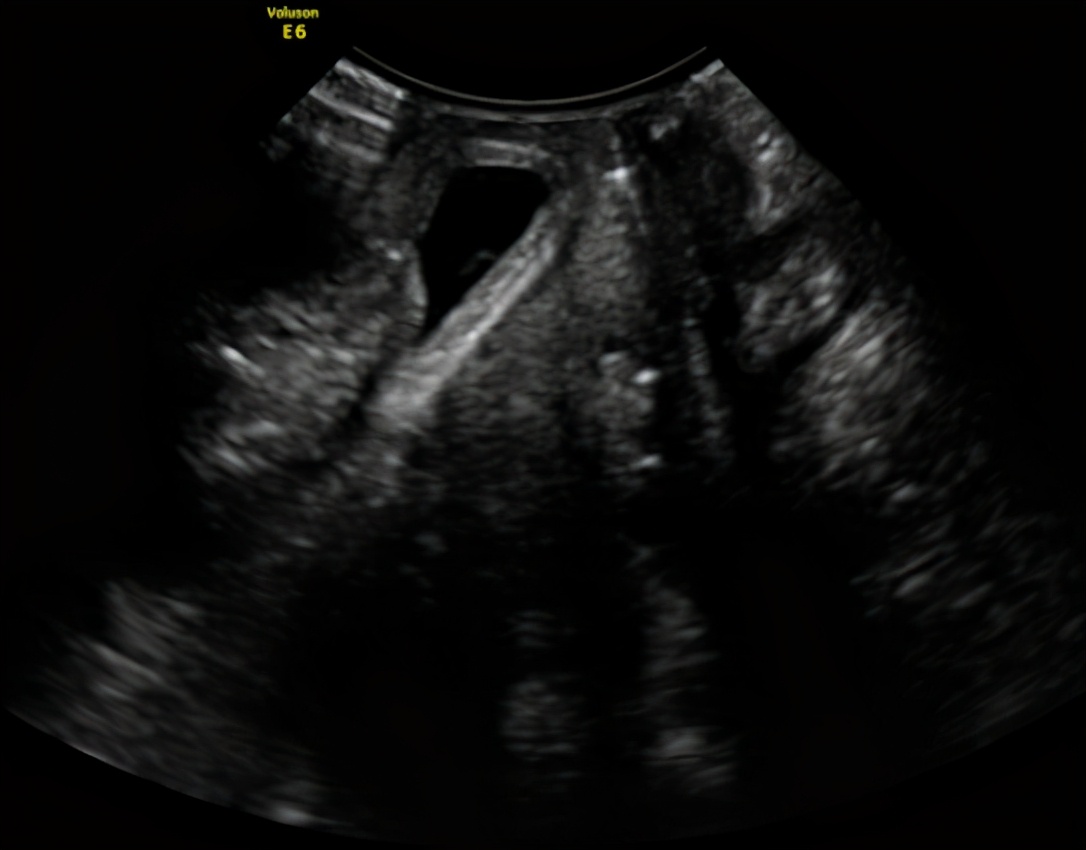

王阿姨的检查结果

(用力状态)